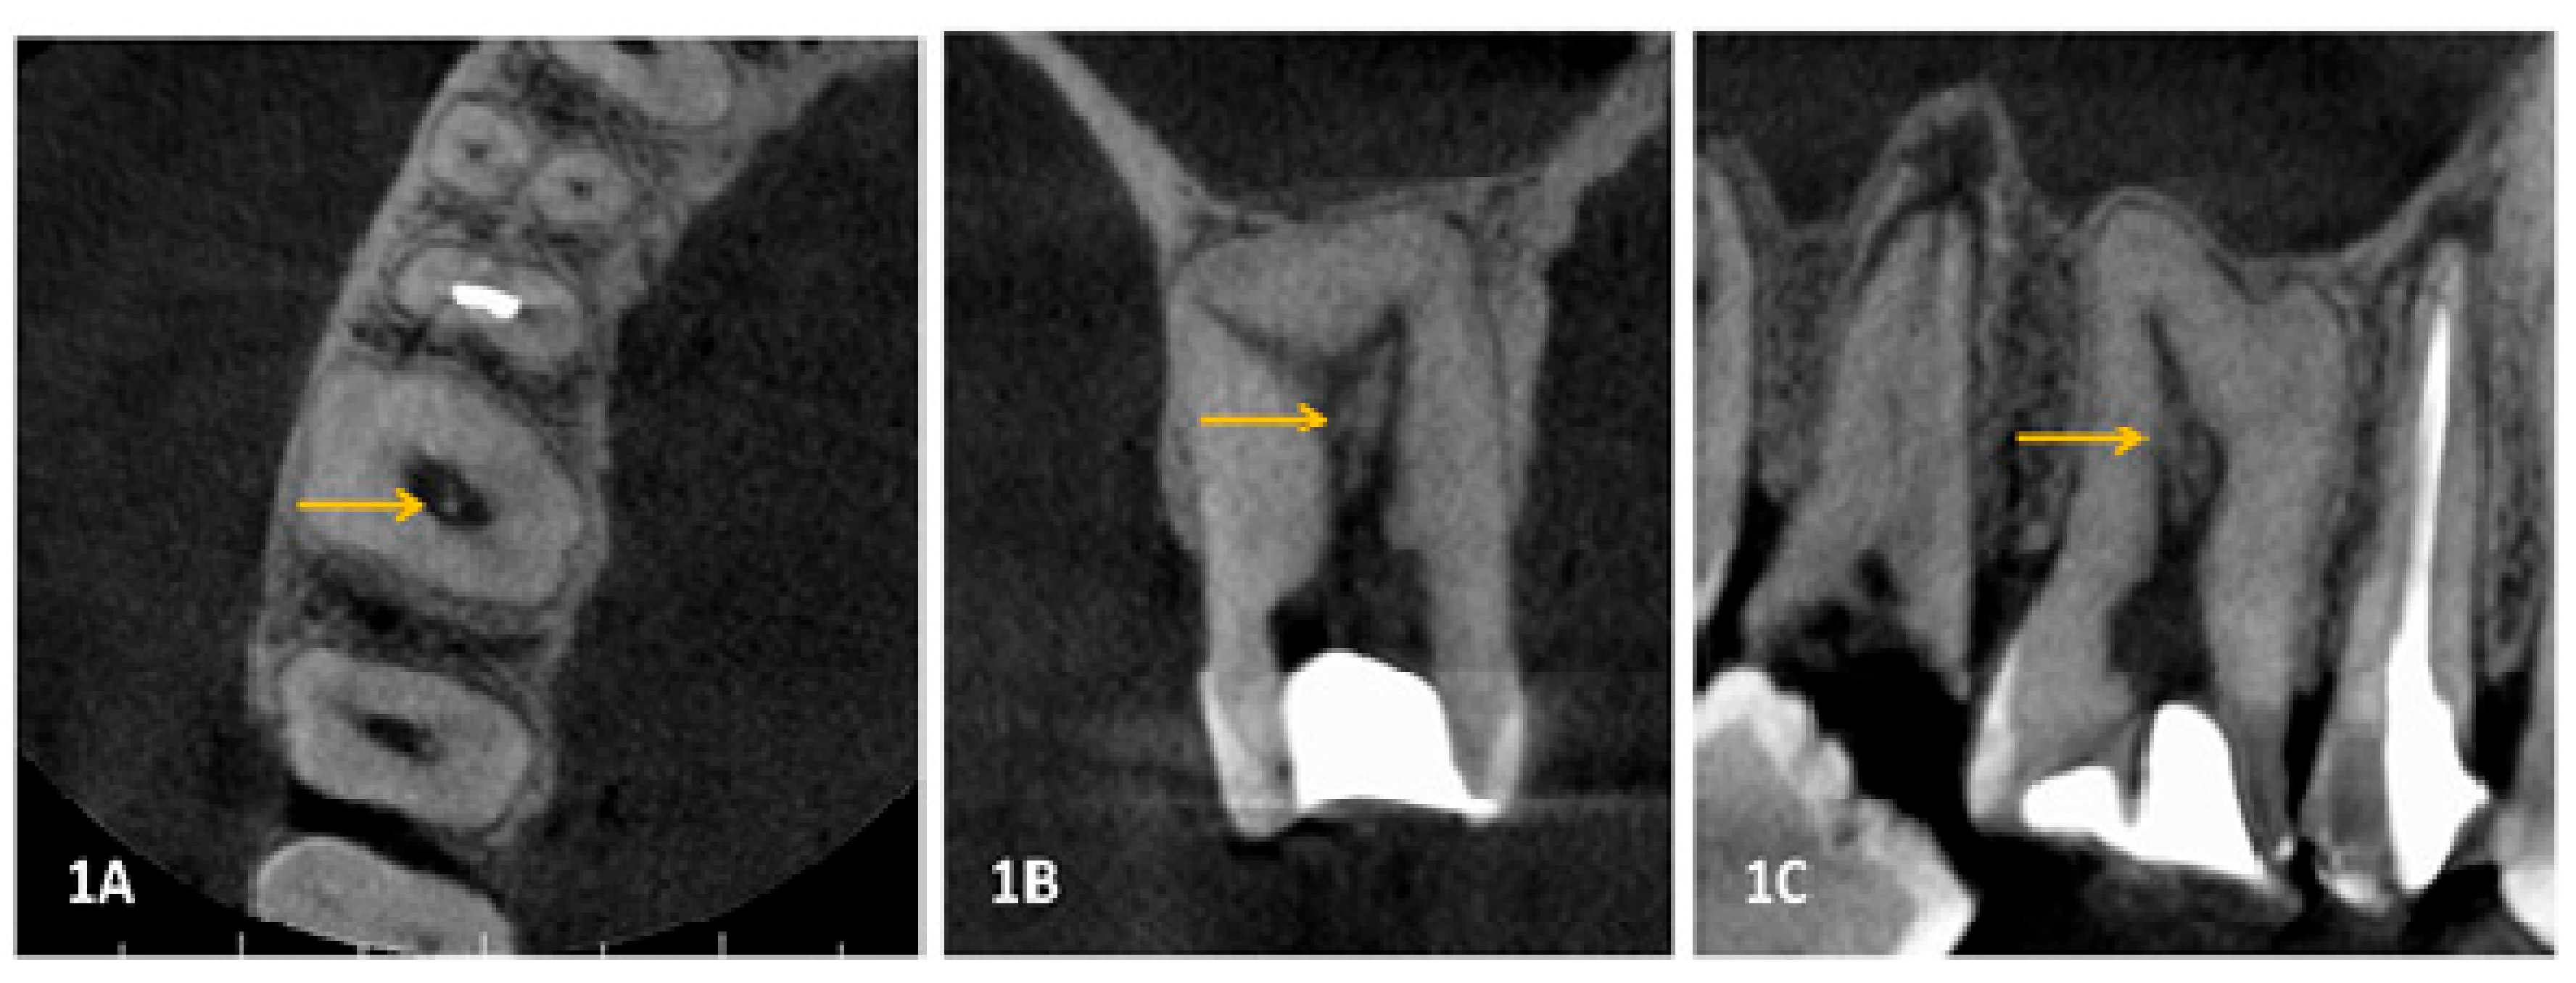

2. Materials and Methods